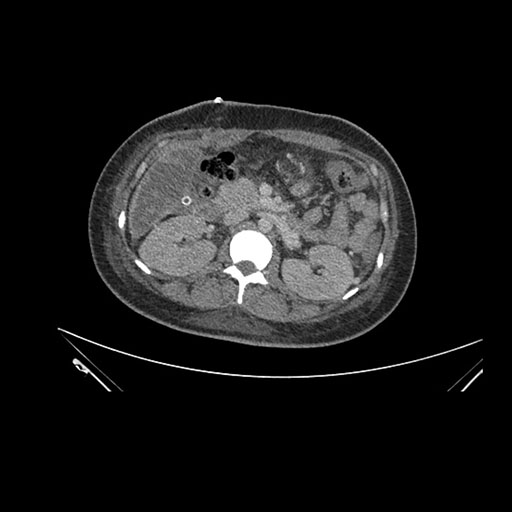

Axial Arterial

Axial Venous